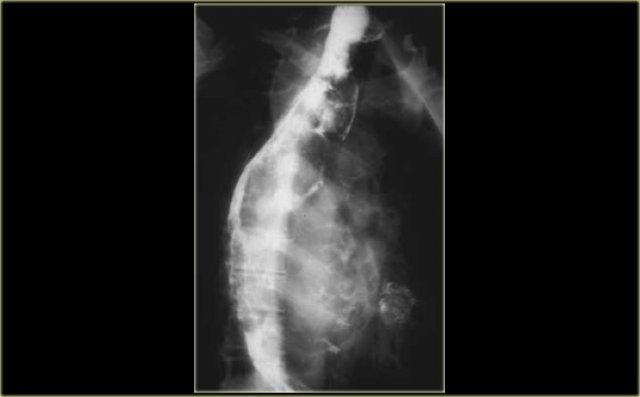

Hình ảnh ngoài cùng bên trái cho thấy thực quản đoạn xa bị hẹp.

Hình chiếu chếch cho thấy ấn lõm thực quản do động mạch chủ với bờ tù (mũi tên), đặc trưng của chèn ép ngoại sinh.

Bệnh lý động mạch chủ

Ngoài cùng bên trái là hình ảnh ấn lõm bình thường của quai động mạch chủ lên thực quản.

Ấn lõm này có thể lớn hơn khi có giãn động mạch chủ như thấy ở bệnh nhân này với phình quai động mạch chủ dạng nấm (mycotic aortic arch aneurysm) (mũi tên).